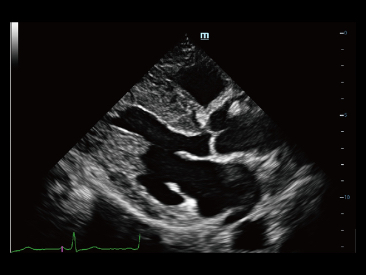

Desde que a empresa foi fundada, a Mindray est├Ī continuamente explorando novas maneiras de melhorar a confian?a no diagn├│stico. Alimentada pela mais revolucion├Īria tecnologia ZONE Sonography?, a nova plataforma Resona 7's ZST+ traz uma qualidade de imagem ultra-som a um n├Łvel superior por aquisi??o de zona e processamento de dados do canal.

Assim como o n├Łvel de qualidade de imagem premium, o Resona 7 tamb├®m melhora as capacidades de investiga??o cl├Łnica com o revolucion├Īrio Fluxo V para avalia??o hemodin?mica vascular e a aquisi??o de plano mais inteligente do conjunto de dados 3D para diagn├│stico CNS fetal. Combinando a opera??o mais intuitiva baseada em gesto de multi-toques e todos os recursos cl├Łnicos essenciais, Resona 7 est├Ī realmente conduzindo novas ondas na inova??o de ultra-som.